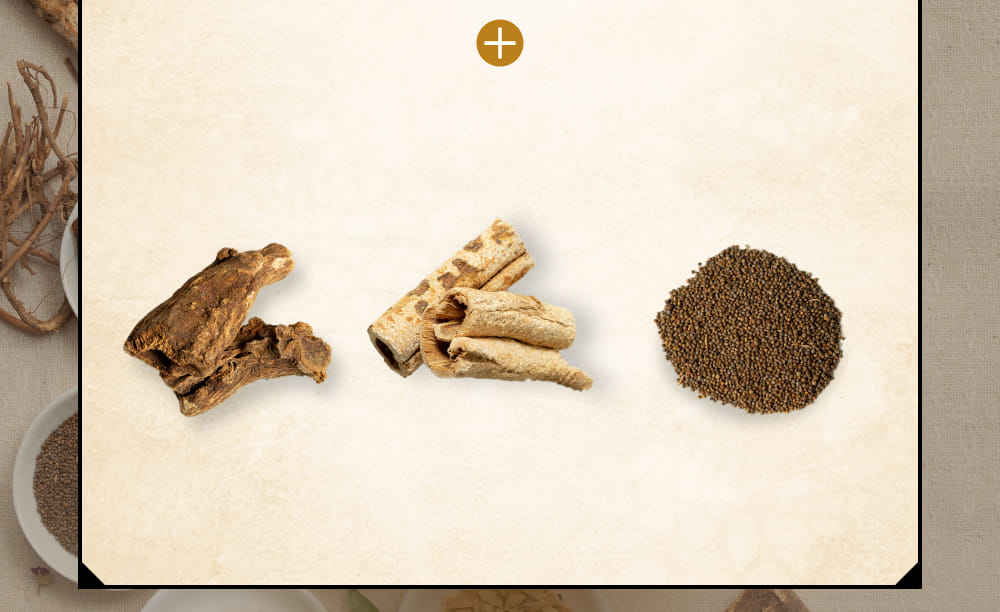

Q.漢方薬とは?

A.漢方薬は「生薬」と

呼ばれる、自然界に存在する

植物・動物・鉱物などの

薬効となる部分を、通常は

複数組み合わせて構成された

薬のことです。

漢方生薬

胆石⋅胆のう炎の疼痛の

炎症緩解に特化した

13種類の

独自配合生薬。

サイコ

セリ科ミシマサイコの根を

乾燥させたもの

効能・効果

消炎・鎮痛作用

ハンゲ

サトイモ科カラスビシャクの

コルク層を

取り除いた

塊茎を乾燥したもの

効能・効果

消化不良改善作用

オウゴン

シソ科のミコガネハナの

根の周皮を除去したもの

効能・効果

解熱・消炎・解毒作用